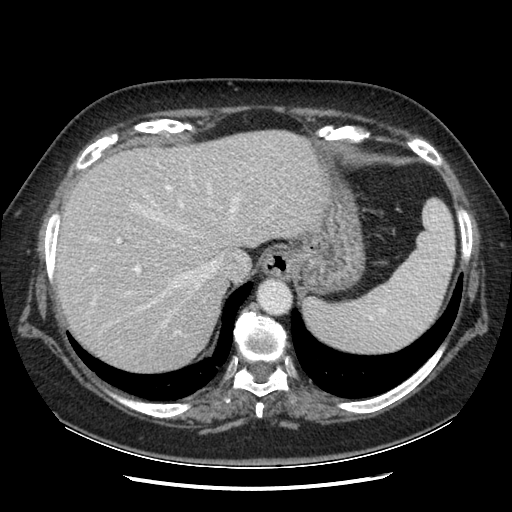

Original VENOUS CT scan

Mediastinum window (WL 40, WW 400 β†’ Low βˆ’160, High +240)